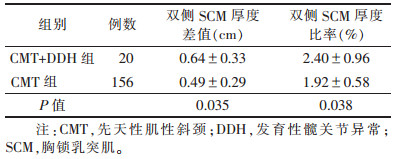

双侧SCM厚度差值和双侧SCM厚度比率(表 2)CMT+DDH组双侧SCM厚度差值和厚度比率均明显高于CMT组(均P < 0.05)。

| 表 2 CMT+DDH组与CMT组双侧SCM厚度差值及比率的比较(x ±s) |

|

本组CMT+DDH组双侧SCM厚度差值和双侧SCM厚度比率均明显高于CMT组(均P < 0.05)。分别以双侧SCM厚度差值≥0.74 cm和双侧SCM厚度比率≥0.24为临界值,预测DDH的敏感度为50.0%和45.0%,特异度为77.6%和83.3%,提示超声检查所示SCM厚度差值和厚度比率对CMT患儿DDH具有一定预测价值,可早期明确2种共存疾病的诊断,有利于患儿进行早期康复治疗,获得最佳治疗效果。